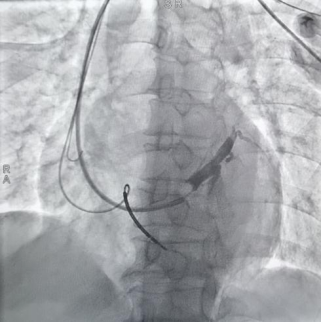

患者造影球囊的造影影像。院方供图

经过周密的术前准备,张亮带领团队在心导管室为患者实施局麻下手术,穿刺左侧锁骨下静脉后,经左室长鞘中置入Amplatz导管找到冠状窦;随后团队使用造影球囊进行冠状静脉造影,经仔细评估确定靶向左室静脉支后,通过精准的导丝操作置入电极,最终顺利完成手术。